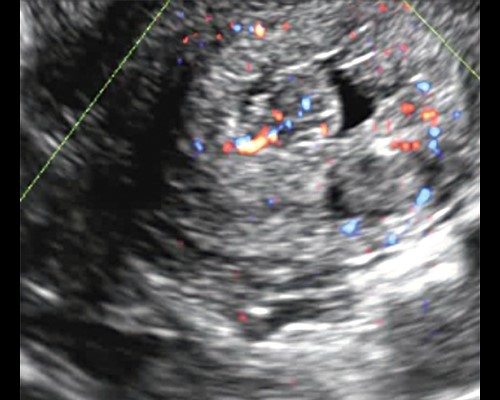

В ходе проводимой нами эхометросальпингографии с использованием в качестве контраста стерильного физиологического раствора также становится возможной визуализация мелких полипов эндометрия и внутриматочных синехий (рис. 3).

Рис. 3. Мелкий полип эндометрия на фоне эхонегативной контрастной среды (стерильный физиологический раствор) в ходе эхогистероскопии.